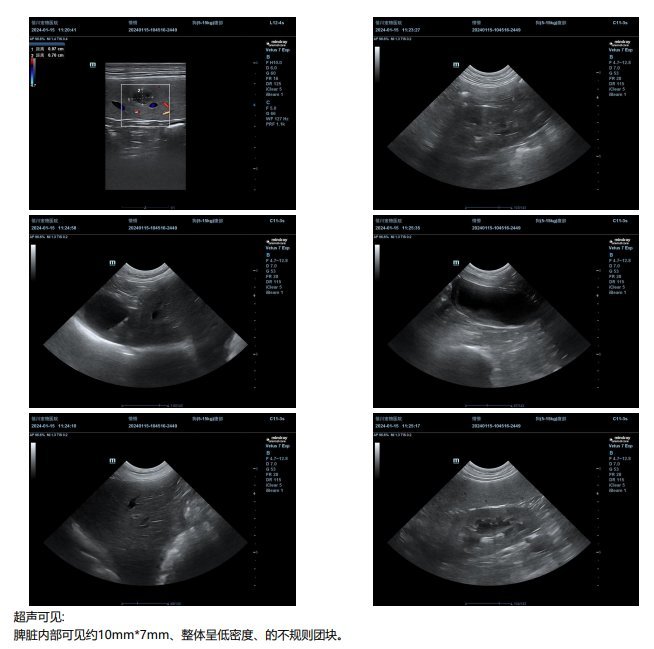

脾囊肿超声图片

图片尺寸780x1052

脾囊肿怎么办,做过相关治疗的家人求给个经

图片尺寸1920x2560